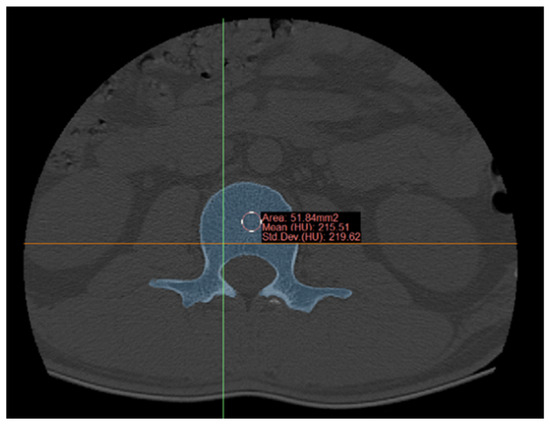

5.1. Data Acquisition and Modeling

5.2. Bone Density Measurement and 3D Printing

- The construction and preparation of lumbar spine models, including the L4 segment and composite vertebral models suitable for 3D printing: Bone density values derived from CT scans of the L4 segmental lumbar spine were integrated into the GA-BP neural network to determine precise 3D printing parameters, facilitating accurate model preparation.